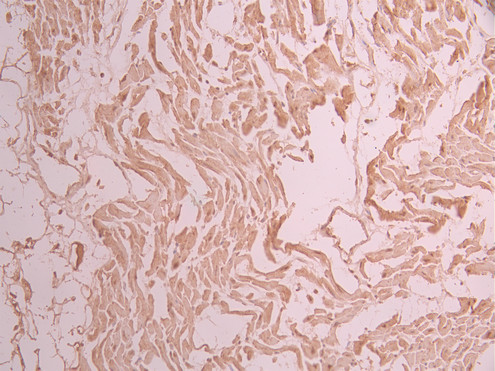

IHC image of CSB-RA448852A0HU diluted at 1:100 and staining in paraffin-embedded human heart tissue performed on a Leica BondTM system. After dewaxing and hydration, antigen retrieval was mediated by high pressure in a citrate buffer (pH 6.0). Section was blocked with 10% normal goat serum 30min at RT. Then primary antibody (1% BSA) was incubated at 4°C overnight. The primary is detected by a Goat anti-rabbit polymer IgG labeled by HRP and visualized using 0.05% DAB.